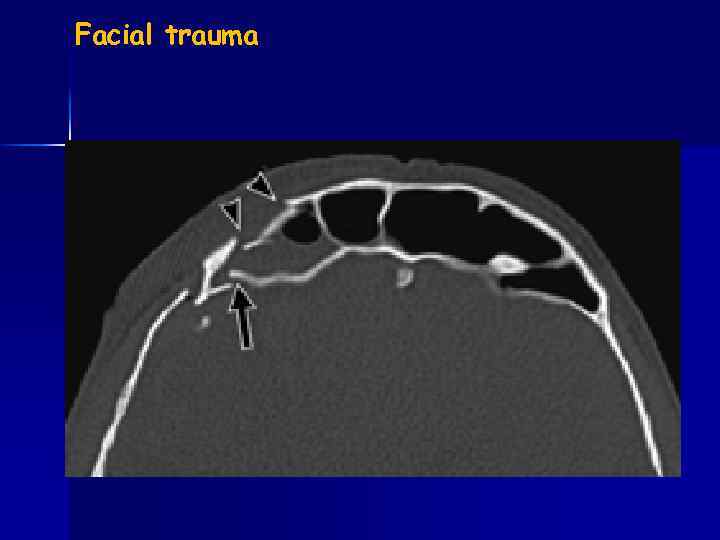

Facial trauma blow-out fracture

Facial trauma

Orbital floor-fx with herniation of fat